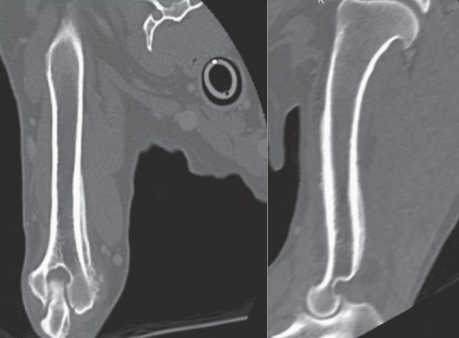

![]() | Thoracic radiographs - pulmonary, mediastinal(์ธ๋ก์นธ) underlying disease ํ์ธ (ex. primary or metastatic neoplasia, granulomatous lesions, heartworm disease; ์๋ฐ์ฑ ๋๋ ์ ์ด์ฑ ์ ์๋ฌผ, ๊ณผ๋ฆฝ์ข ์ฑ ๋ณ๋ณ, ์ฌ์ฅ์ฌ์์ถฉ ๋ฑ) |

![]() | - ํ๋ถ ์งํ ์๋ณ X โ ๋ณต๋ถ ์งํ ์๋ณ (๋ณต๋ถ ์ด์ํ) - ์ผ๋ถ ๊ฒฝ์ฐ ์๋ฐ ๋ณ๋ณ์ ํ์ธํ๊ธฐ ์ํด CT, MRI๊ฐ ํ์ํ ์ ์๋ค. |